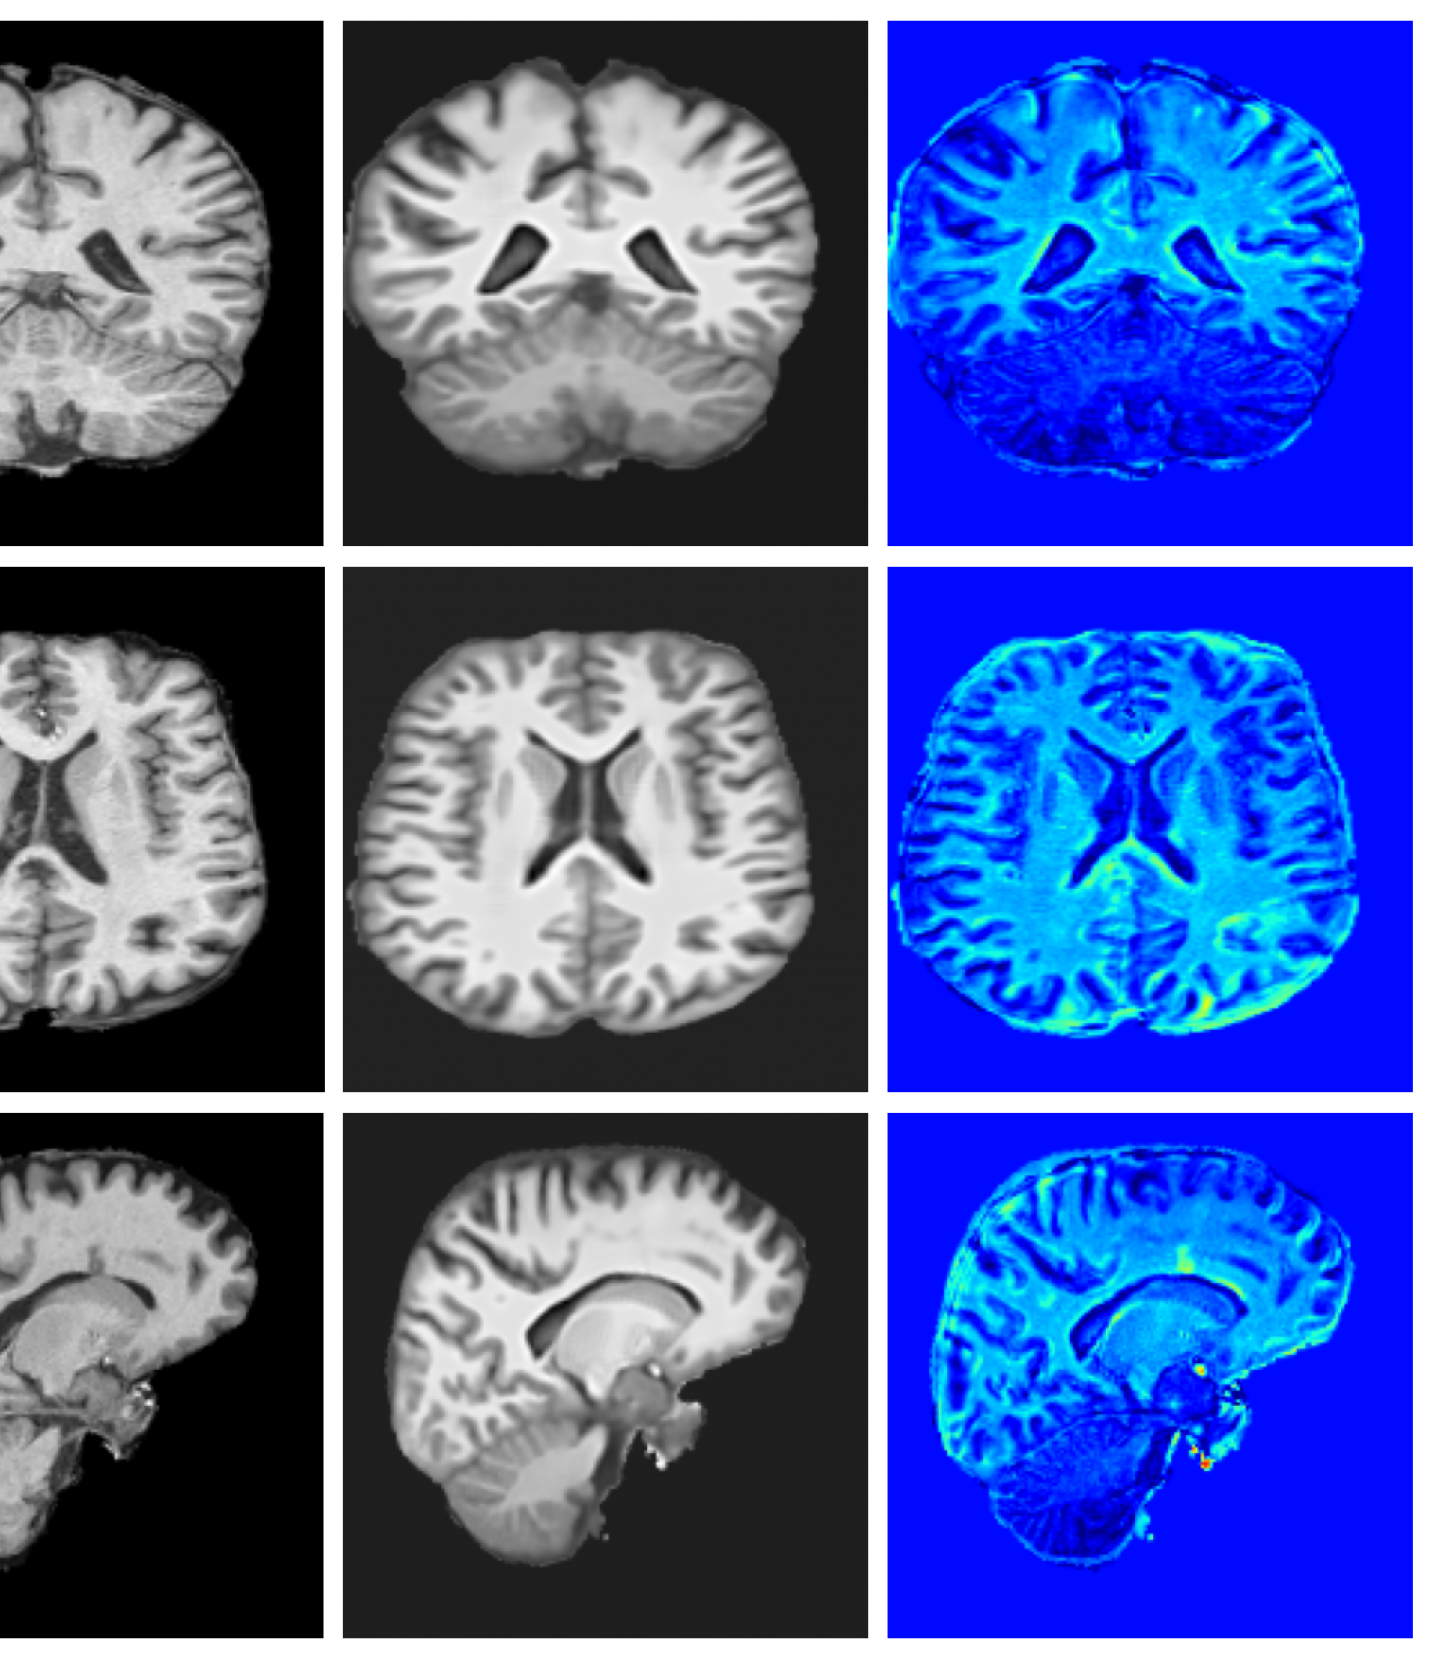

Qualitative T1w results are shown in Figure 2, with further examples for other modalities in Appendix A.8. LoHiResGAN and Res-SRDiff produce unrealistic images with severe artifacts, likely arising from bias fields, sharp intensity artifacts, and other noise not present during training. UniRes generates oversmoothed images, likely due to its TV prior and its reliance on information from multiple input modalities, whereas we apply it unimodally. SynthSR, like our method, preserves key anatomical structures; however, our difference maps show reduced contrast, further supporting the strong quantitative results shown in Table 1.

A.8 Additional qualitative restoration results

Additional qualitative results for the Clinical dataset are given in Figures 7, 8 and 9, and for the Low-field dataset in Figures 10 and 11.